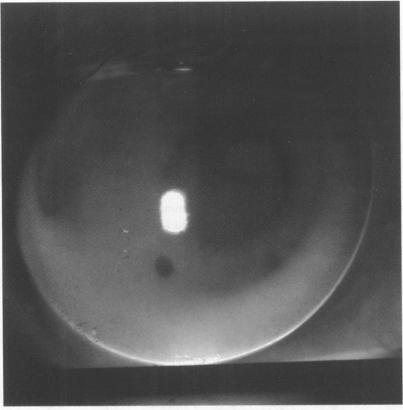

准分子激光角膜切削术后的隐形眼镜验配

Contact lens fitting after photorefractive keratectomy.

AIMS/BACKGROUND: This study evaluated contact lens fitting and the longer term response of the photorefractive keratectomy (PRK) cornea to lens wear. In PRK for myopia problems such as regression, anterior stromal haze, irregular astigmatism, halo aberration, and anisometropia have been reported. Certain patients therefore require contact lens correction to obtain best corrected visual acuity (BCVA).

The best fit rigid gas permeable lens of diameter 9.20-10.00 mm was generally 0.10 mm steeper than mean keratometry readings. Because of lid discomfort five patients were refitted with daily wear soft lenses. All 10 achieved satisfactory lens wear of 10 hours per day. Central corneal steepening of 0.75 D (0.15 mm) occurred in one patient. Two patients had slight central corneal flattening. Three patients discontinued lens wear as they found lens care a nuisance. Four finally opted for retreatment by PRK.

CONCLUSIONS

In most cases, contact lenses gave good visual acuity and, in cases of mild irregular astigmatism, a significant improvement over spectacle BCVA. No significant adverse reaction to contact lens wear was found. Although ocular tolerance of lenses was satisfactory, several patients discontinued lens wear or sought improved unaided vision.